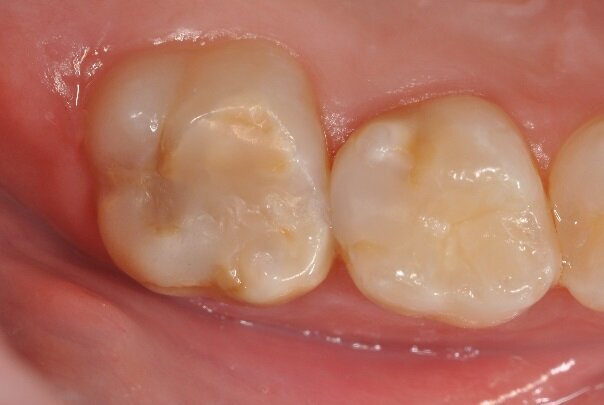

Restoration with resin composite is the treatment of choice for MIH-affected teeth. The resin effectively seals the affected surface, and composite is considered a good insulator against harmful substances. In addition, healthy hard tooth substance can be optimally preserved, since the filling material is directly bonded. Amalgam is contra-indicated as a filling material for MIH-affected teeth. (Photograph: Prof. Norbert Krämer)

The photograph shows a mild form of MIH. Discoloration indicating the soft enamel can be seen on the occlusal surface of the molar. An important characteristic of such enamel is a hardness reduced by a factor of ten, resulting in likely caries and infraction of the surface under masticatory load. (Photograph: Prof. Norbert Krämer)